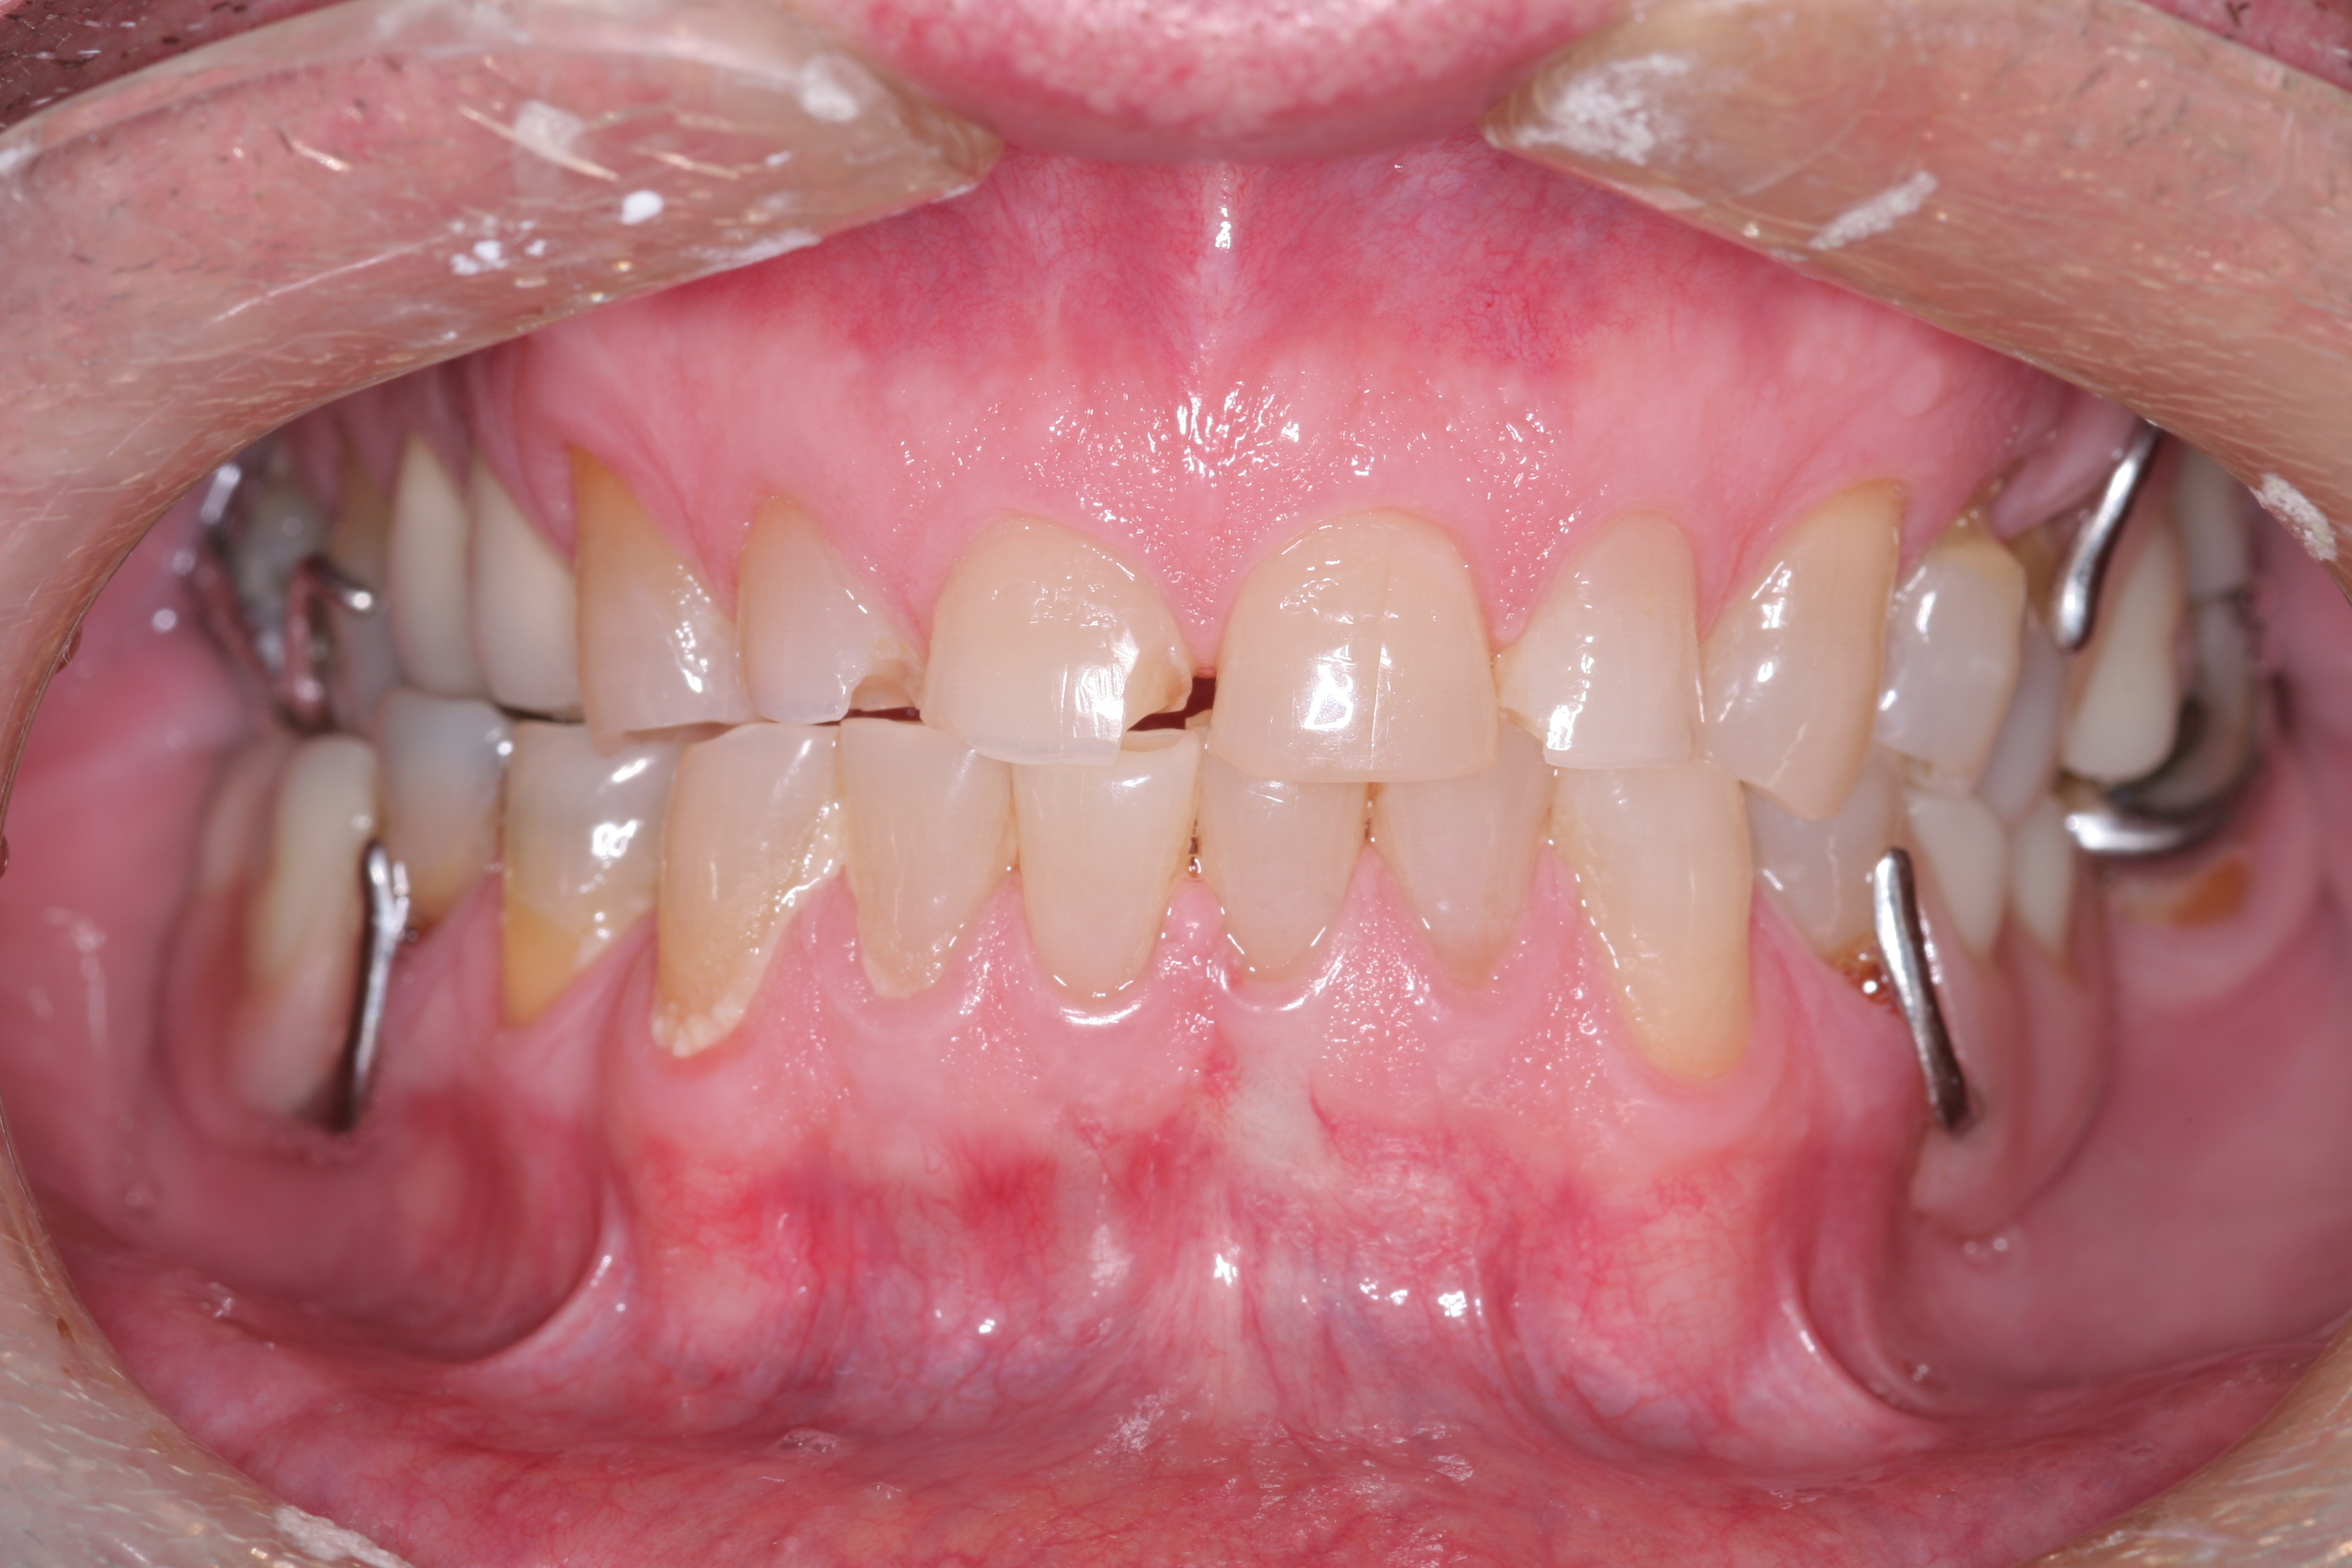

(3.) Either form of parafunction, whether conscious or unconscious, involves excessive rubbing together of the dentition.

Figure 3

(4.) CR/MIP discrepancies are very common and are major factors leading to excessive tooth-to-tooth abrasion.

Figure 4

True parafunctional bruxism is often rooted in central nervous system–mediated factors and can be influenced by psychosocial and peripheral factors.6 Parafunction may be conscious or unconscious. Either form involves excessive rubbing together of the dentition (Figure 3). CR/MIP discrepancies are very common and are major factors leading to excessive tooth-to-tooth abrasion (Figure 4). CR is the stable axial position the condyle reaches in the most superior and medial aspect of the glenoid fossa. According to Dawson, CR is the only condylar position that allows an interference-free occlusion.1 When the muscles of mastication contract, the condyles will seat into this anatomical position as long as there are no tooth contact interferences preventing the seat. Ideally, when a person closes, the joint will stay seated in CR and all the teeth will come in contact at the same time. Harmony will exist between seated joints and tooth contact.1 If the condyle is seated and the mandible rotates to allow full intercuspation, and posterior tooth inclines contact first, then the mandible slides down and forward around the interferences so that full tooth intercuspation can occur. However, this causes the condyle to be pulled out of CR and braced down the articular eminence by the lateral pterygoid muscle.7 This lack of harmony causes excessive wear as the teeth try to dictate MIP and the muscles work to seat the joint fully into CR. Tooth structure will often lose this “war” between muscles and teeth, resulting in excessive wear or breakage. Symptoms can also be evident in the temporomandibular joints (TMJs) and muscles themselves. This is why a complete examination reviewing all components of the stomatognathic system is critical. Although this topic is beyond the scope of this article, a complete diagnosis cannot be stressed enough.